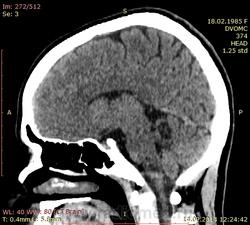

Мало того в левом полушарии мозжечка - гиподенсивный округлый участок без объемного воздействия. Плотность не ликворная. Киста? Образование?

Уважаемый, Коллега! Разрешите Вас поправить: исследование не ушей, а височных костей. В отношении Лор-патологии А.Ю. коротко Вам написал. Но после Вашего исследования, для пациента наиболее важным становится анализ кистоподобного образования мозжечка, которое в диф. диагностике может быть: от кисты - до онкологии. И теперь для Вас, как для врача лучевой диагностики стоит задача возможными методиками или др. методом определить характер пат. зоны. Либо КТ, либо МРТ с внутривенным контрастированием.